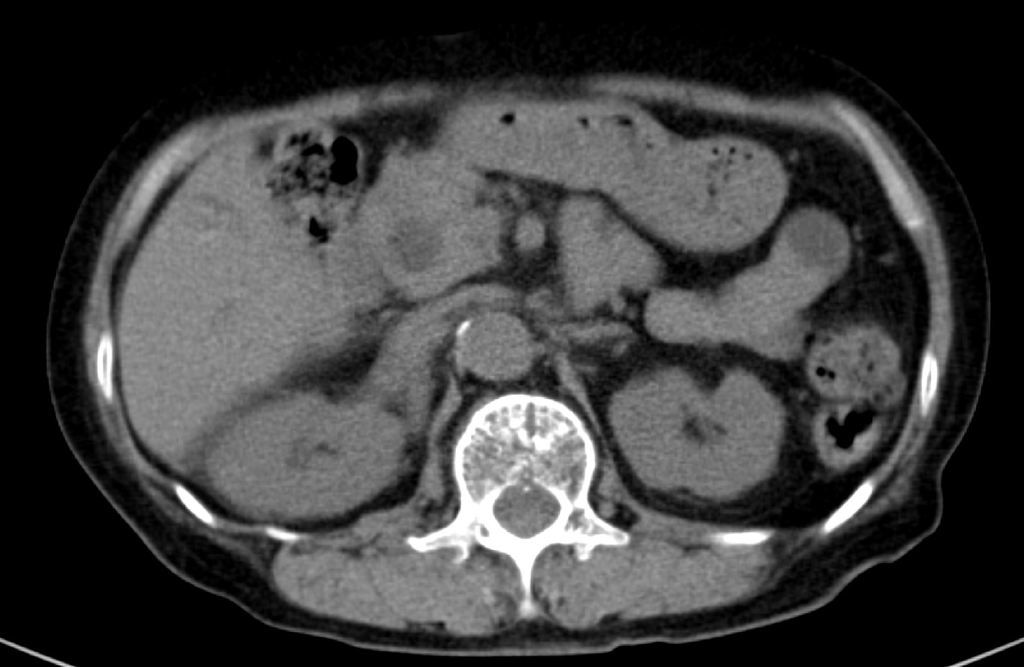

총수담관의 아래쪽 끝부위를 종단면스캔한 영상입니다. 앞서 보였던 담관결석과 총수담관의 갑작스러운 폐쇄가 보입니다. 앞서 보였던 총수담관 벽이 두꺼워지고 총수담관의 급격한 폐쇄는 근처에 경계가 불분명한 침윤성 병변의 가능성을 제기할 수 있는 소견입니다. 즉, CBD cancer의 가능성까지 의심해볼 수 있는 영상소견이지요.

이처럼 CT에서는 전혀 확인할 수 없었던 간외담관의 결석 및 담관암 의심소견을 초음파 영상에서는 비교적 쉽고 명확하게 확인할 수 있는 사례였습니다. 실제 담관의 확장이 있는 경우 위와 같이 CT에서는 전혀 보이지 않는 병변을 초음파영상에서 확인하는 경우가 꽤 흔합니다. 이러한 경험을 많이 하지 않은 분들이 CT의 유용성을 마치 만능에 가까운 것처럼 착각하는 경우가 있습니다만, 실제로는 이번 사례처럼 그렇지 않습니다.

간혹 초음파영상이 검사하는 사람의 경험과 노력에 따라 민감도나 특이도 편차가 크기 때문에 불안을 느껴서 CT를 초음파영상보다 더 신뢰하게 되는 경우가 있는데, CT나 초음파 영상 모두 어느 한쪽을 완전히 대체할 수 없는 영상검사라는 점을 잊어선 안됩니다.